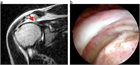

1. 外傷歴のはっきりしない腱板断裂や無症候性腱板断裂が存在する(推奨度2)

1. このような腱板断裂は、炎症性疼痛のコントロールと肩甲胸郭機能の修正を図る理学療法で多くは症状が軽減する(推奨度2)

1. 逆に比較的若年男子の外傷性腱板断裂で大きな断裂は、可及的早期(受傷後2カ月以内)の手術が推奨される(推奨度2)